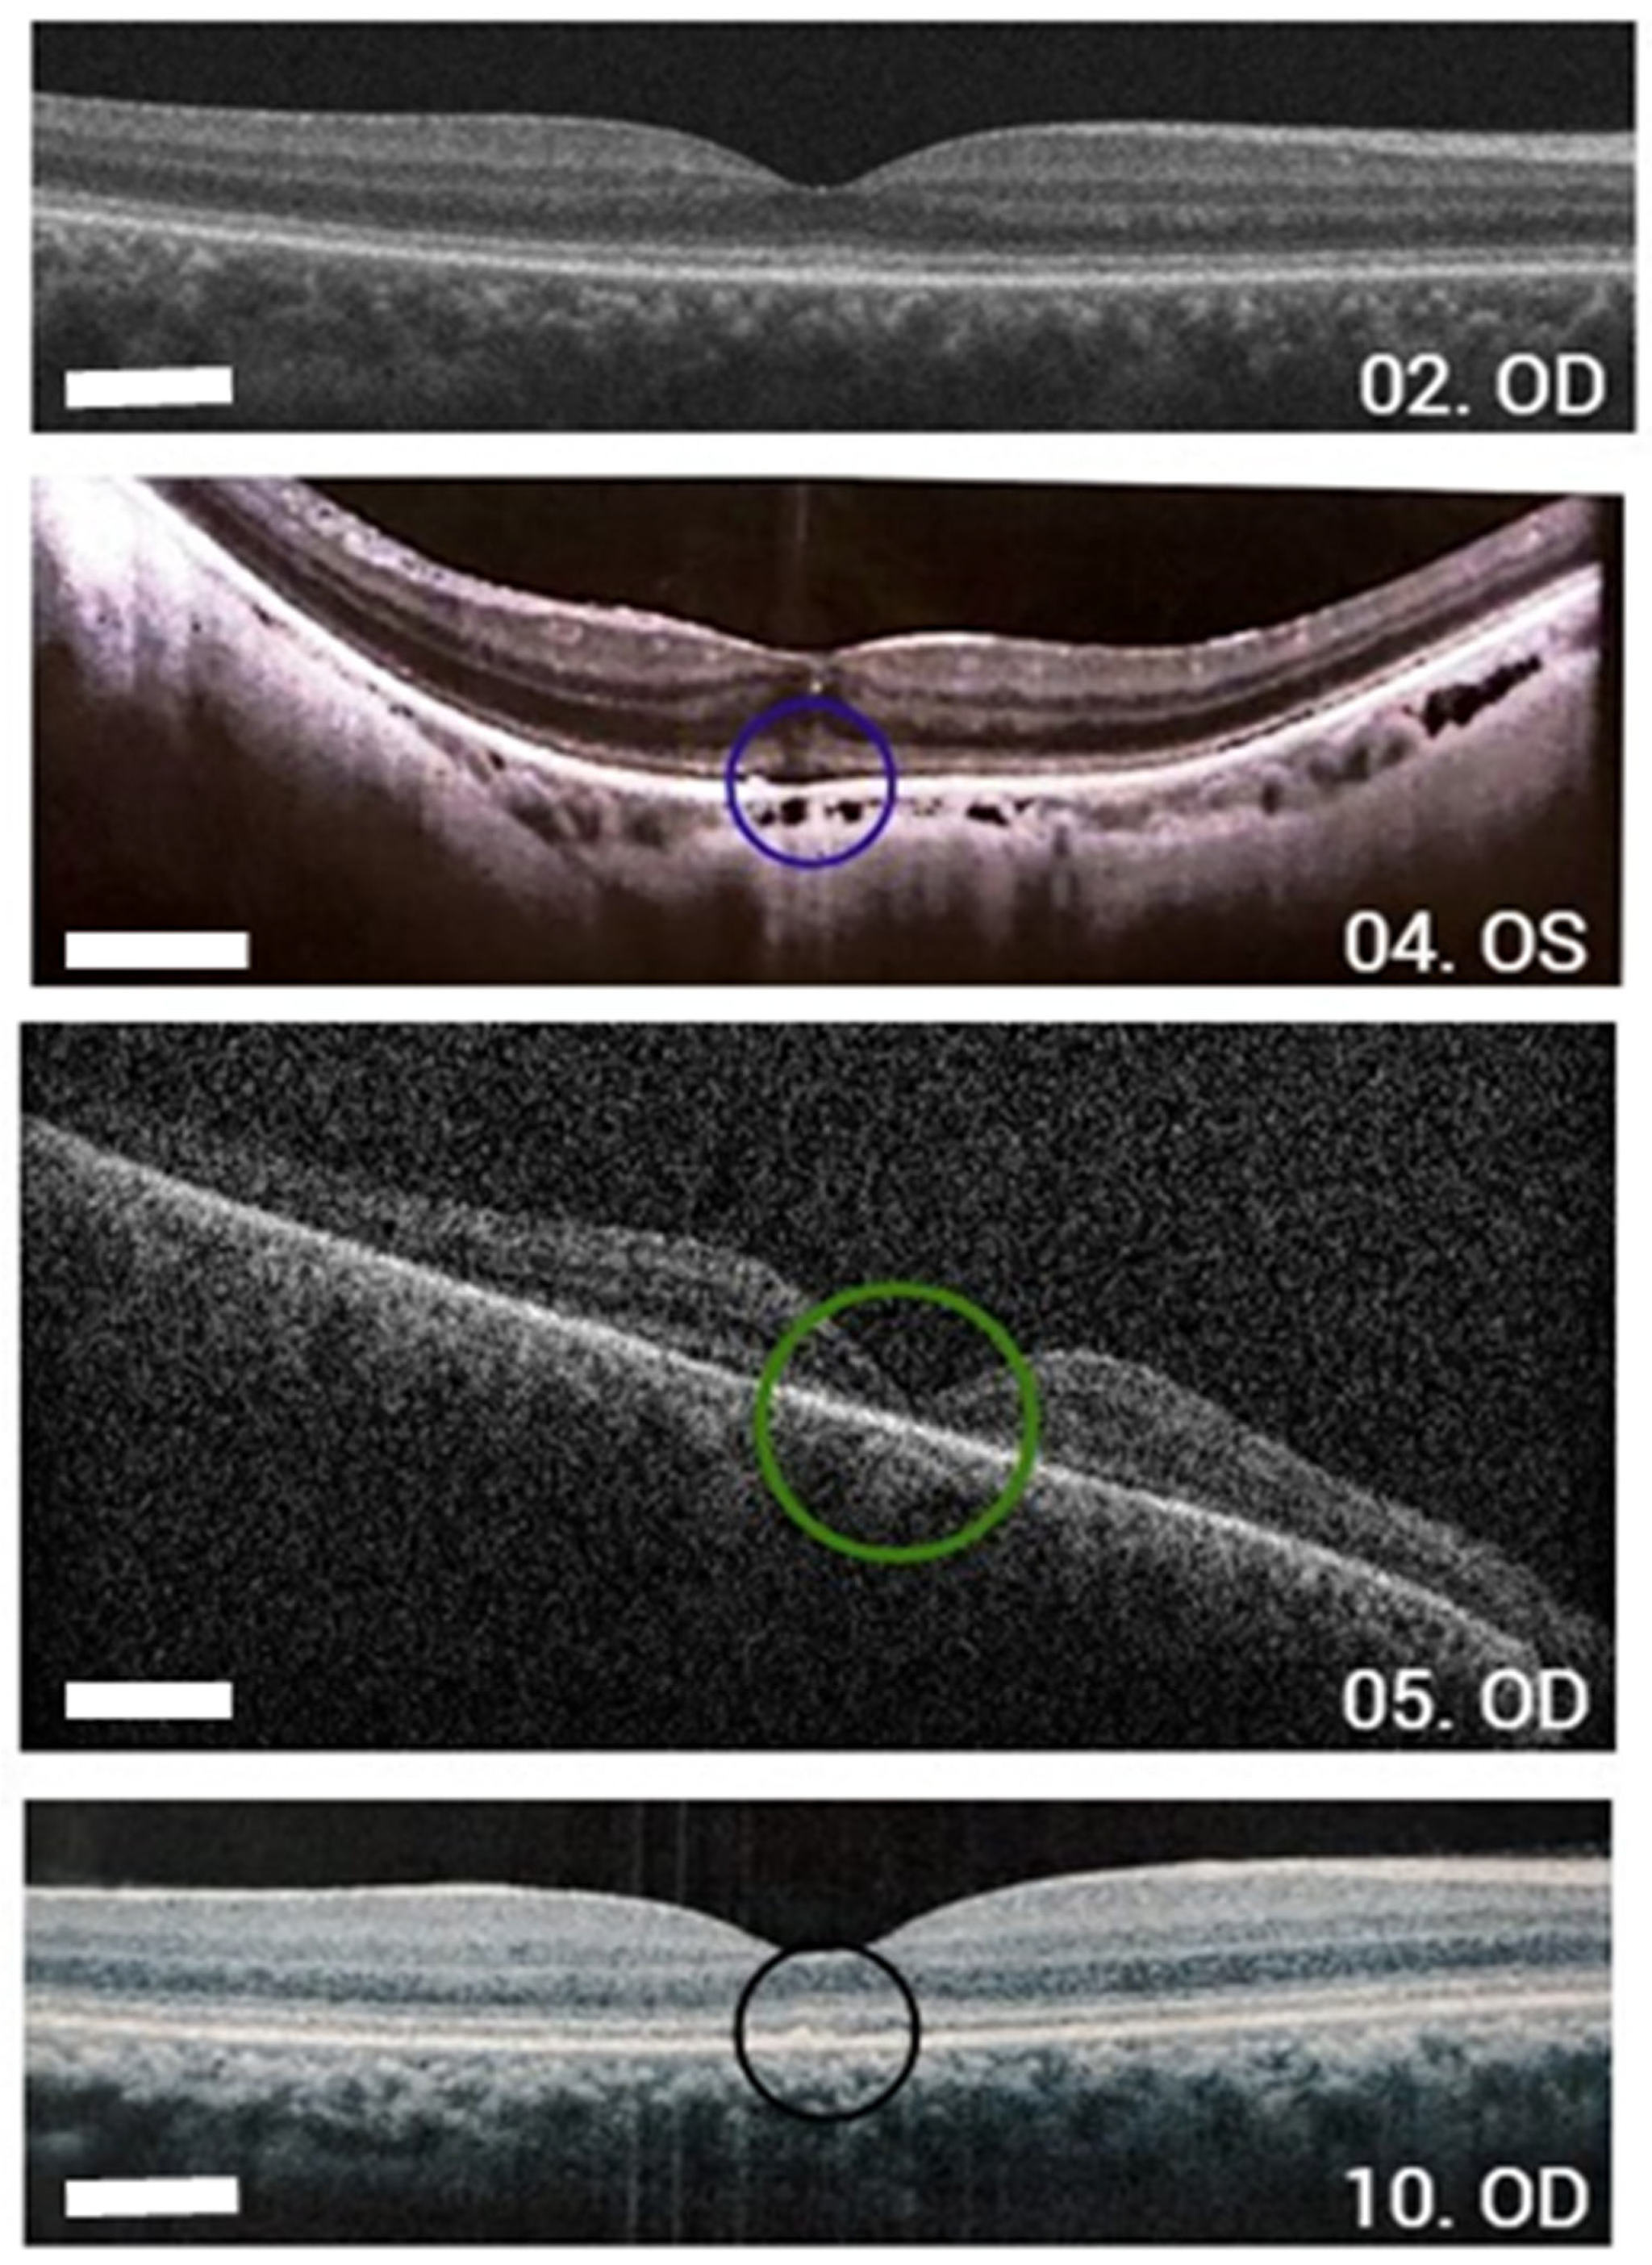

| 04 | c.1052A>G (p.Tyr351Cys) | c.1052A>G (p.Tyr351Cys) | F | 55 | 20/80 OD–20/70 OS | Night blindness since childhood, myopia | Yes (hypertrophy of RPE foveal) OD, foveal hyper-autofluorescence OS |

| 05 | c.1972C>T (p.His658Tyr) | c.1972C>T (p.His658Tyr) | M | 37 | HM OU | Consanguineous parents Keratoconus, corneal leucoma in OS | Bull’s eye OU, ring hypo-autofluorescence around the fovea. |

| 10 | c.2302C>T (p.Arg768Trp) | c.767A>C (p.Gln256Pro) | F | 23 | 20/150 OU | Change in macular brightness | Foveal RPE atrophy, foveal hyper-autofluorescence with hipo-autofluorescence areas OU |